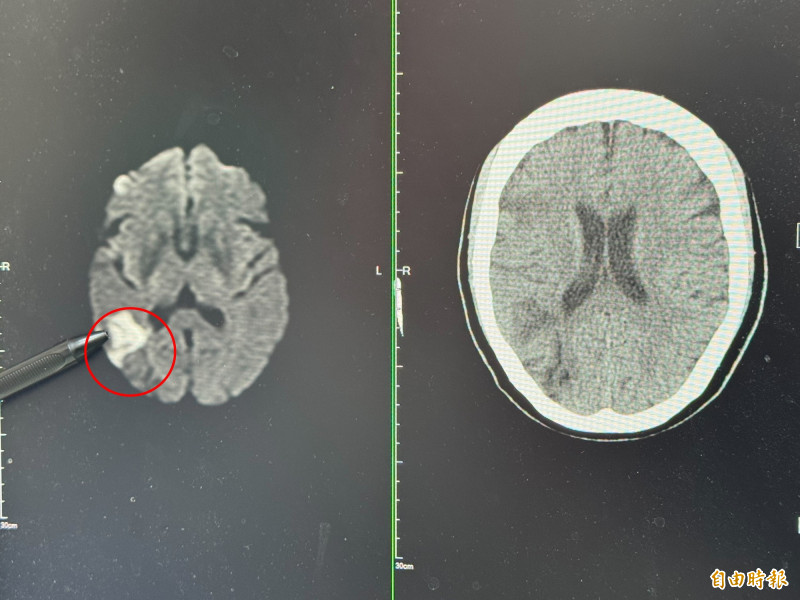

張峻誠說,電腦斷層檢查,果然看到右邊中大腦動脈阻塞,進一步做核磁共振,詳細判讀後發現,婦人當時眼睛出現模糊時已經初次中風,只是比較幸運範圍較小,沒有出現手腳無力、無法行走的情形。

張峻誠指出,婦人患有三高,尤其膽固醇嚴重超標,非典型中風指中風症狀不是臉歪嘴斜、單側無力或口齒不清,而是會出現像婦人一樣,有突然視野缺損或視力模糊,另外,可能出現的症狀,還包含突然頭暈合併平衡感喪失、認知功能障礙、意識改變,或是單側肢體不自主運動等,因血管阻塞的位置較特殊,才沒有出現常見的中風症狀。